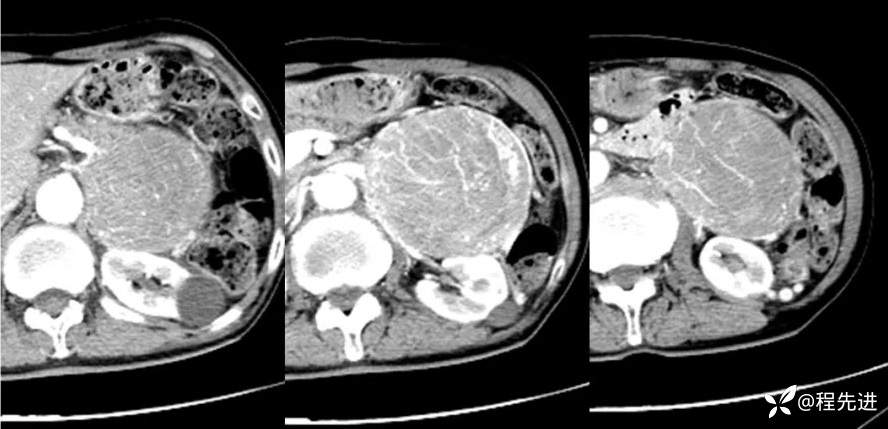

CT增强:

动脉早期: